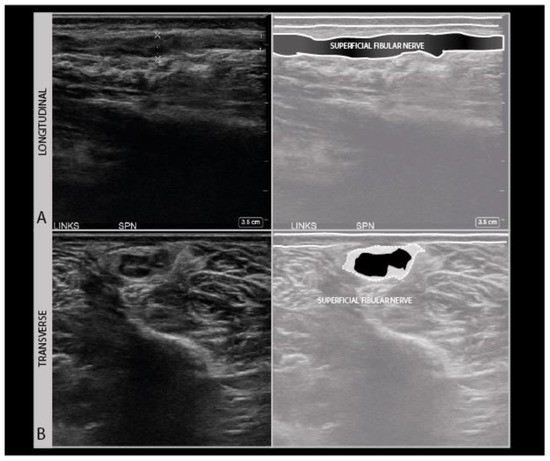

As a standard in neurological nerve ultrasound, transverse imaging is performed for the anatomical identification of the nerve of interest, and to assess its size and architecture for abnormalities. The international agreement is that the nerve size is best measured as a cross-sectional area (CSA) of the nerve traced within the hyperechoic outer epineurial rim [17]. Tracing within the epineurium is the best way to standardize the measurements across patients and over time, as the outer parts of the epineurium blend into surrounding epimysium and fascial structures, which hampers the accurate delineation of the nerve. CSA reference values are available for many nerves [18]. Nerve size increases during growth, so for schoolchildren it is advisable to adhere to a reference that is 50–75% of the adult size depending on age [19].

To assess the nerves for abnormality, it is strongly advised to scan the nerve all the way along its accessible length, looking for sudden changes in size or appearance. When an abnormality is found, it is advisable to also twist the probe 90° around and make a longitudinal image of the lesion site. When measuring neuroma sizes, placing several diameter markers proximal, at and caudal to the lesion site may be helpful (Figure 3).

Figure 3.

Image examples of transverse cross-sectional area (CSA) (A) versus longitudinal diameter measurement (B). A: distal ulnar neuroma; B: distal median nerve neuroma (adult male with a crush injury of the distal forearm). ULN = ulnar nerve.

Longitudinal images are not very good for the identification of the anatomical location, but they are more intuitive for looking at pathology by referring physicians (or patients). It is advisable to annotate images with sparse text to indicate the site, including a nerve name abbreviation such as “MED” for the median nerve, and an indicator for left/right, distal/proximal, etc.). For any nerve that could require surgical intervention, it is recommended to measure the site of abnormality in reference to a recognizable anatomical landmark (e.g., “5 cm distal from the intermalleolar line, 2 cm lateral from the midline” etc.). We strongly recommend making a short ultrasound video scanning from the proximal across a lesion site to a distal one, as ultrasound videos are much easier to interpret afterwards than still images. Finally, the images should be saved to a network location or printed to be saved with the patients’ health records.